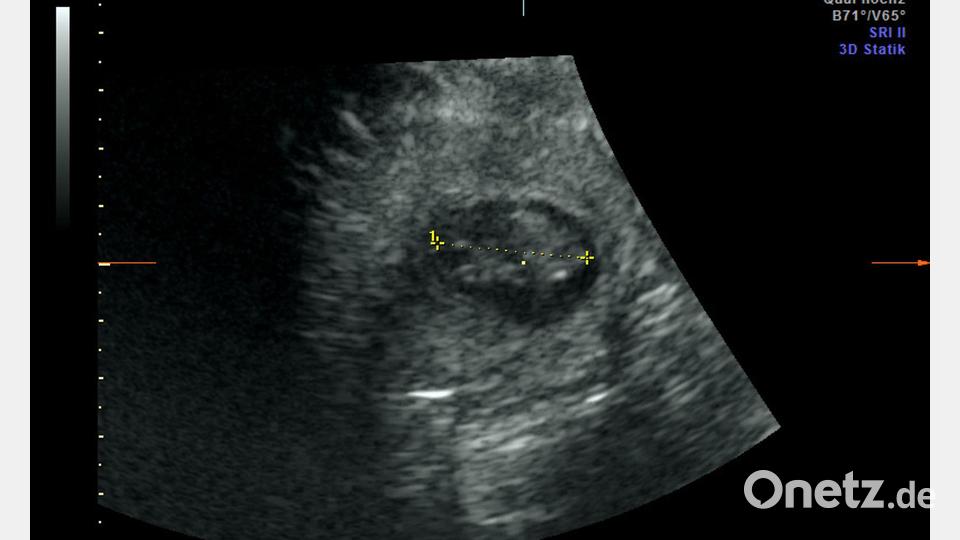

Im Berliner Zoo wird wieder Panda-Nachwuchs erwartet. „Die Babys sind etwa 2,5 Zentimeter groß und müssen jetzt bis zur Geburt noch ordentlich wachsen“, sagte Thomas Hildebrandt, Leiter der Abteilung für Reproduktionsmanagement am Leibniz-Institut für Zoo- und Wildtierforschung laut Pressemitteilung. Im Panda Garden sei am Sonntag ein kleiner Jubel ausgebrochen, teilte der Zoo mit. Die Panda-Dame hatte sich zuletzt nicht besonders kooperativ gezeigt. „Trotz sichtlichen Bauchkneifens“ habe Meng Meng sich aber überzeugen lassen, „in den aufrechten Stand zu kommen und das kühle Ultraschall-Gel sowie die Untersuchung mit der Ultraschall-Sonde zu akzeptieren“, sagte der Veterinärmediziner, der als internationaler Experte bei der Reproduktion von Großen Pandas gilt. „Eine Untersuchung im Stehen hat schließlich die freudige Nachricht gebracht, dass Meng Meng mit zwei Jungtieren trächtig ist.“

Die Freude im Team sei riesig gewesen, weil es schon einige erfolglose Ultraschallversuche gegeben habe, sagte Zootierärztin Franziska Sutter, die ebenfalls an der Untersuchung beteiligt war. „Bei aller Begeisterung müssen wir uns darüber im Klaren sein, dass das ein sehr frühes Stadium der Trächtigkeit ist und eine sogenannte Resorption – also ein Absterben - des Embryos zu diesem Zeitpunkt noch möglich ist“, sagte Sutter. Die Tragzeit beträgt bei Großen Pandas in der Regel drei bis sechs Monate.